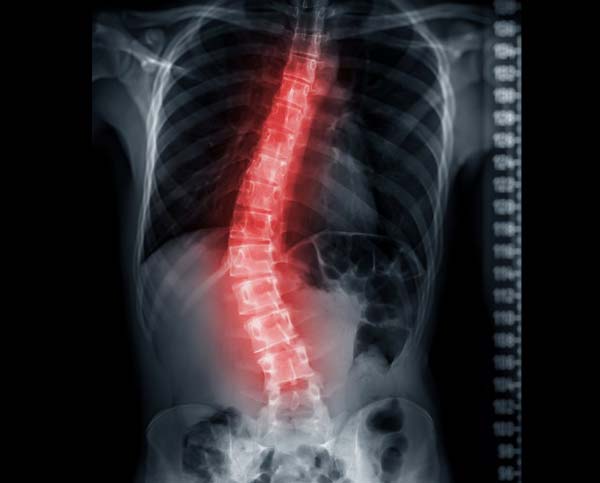

척추측만증 진단에서 가장 중요한 것은 엑스레이 사진이다. 척추 전체를 촬영해 측만 위치와 몸의 균형을 확인할 수 있으며, 하지도 함께 촬영해 다리 길이의 차이에서 오는 영향을 판단한다. 신체검사로도 측만증 유무를 감별할 수 있다. 다른 원인이나 관련 증상을 감별하기 위해 어깨 높이와 견갑골 위치, 관절운동 이상 여부를 검사하기도 한다.